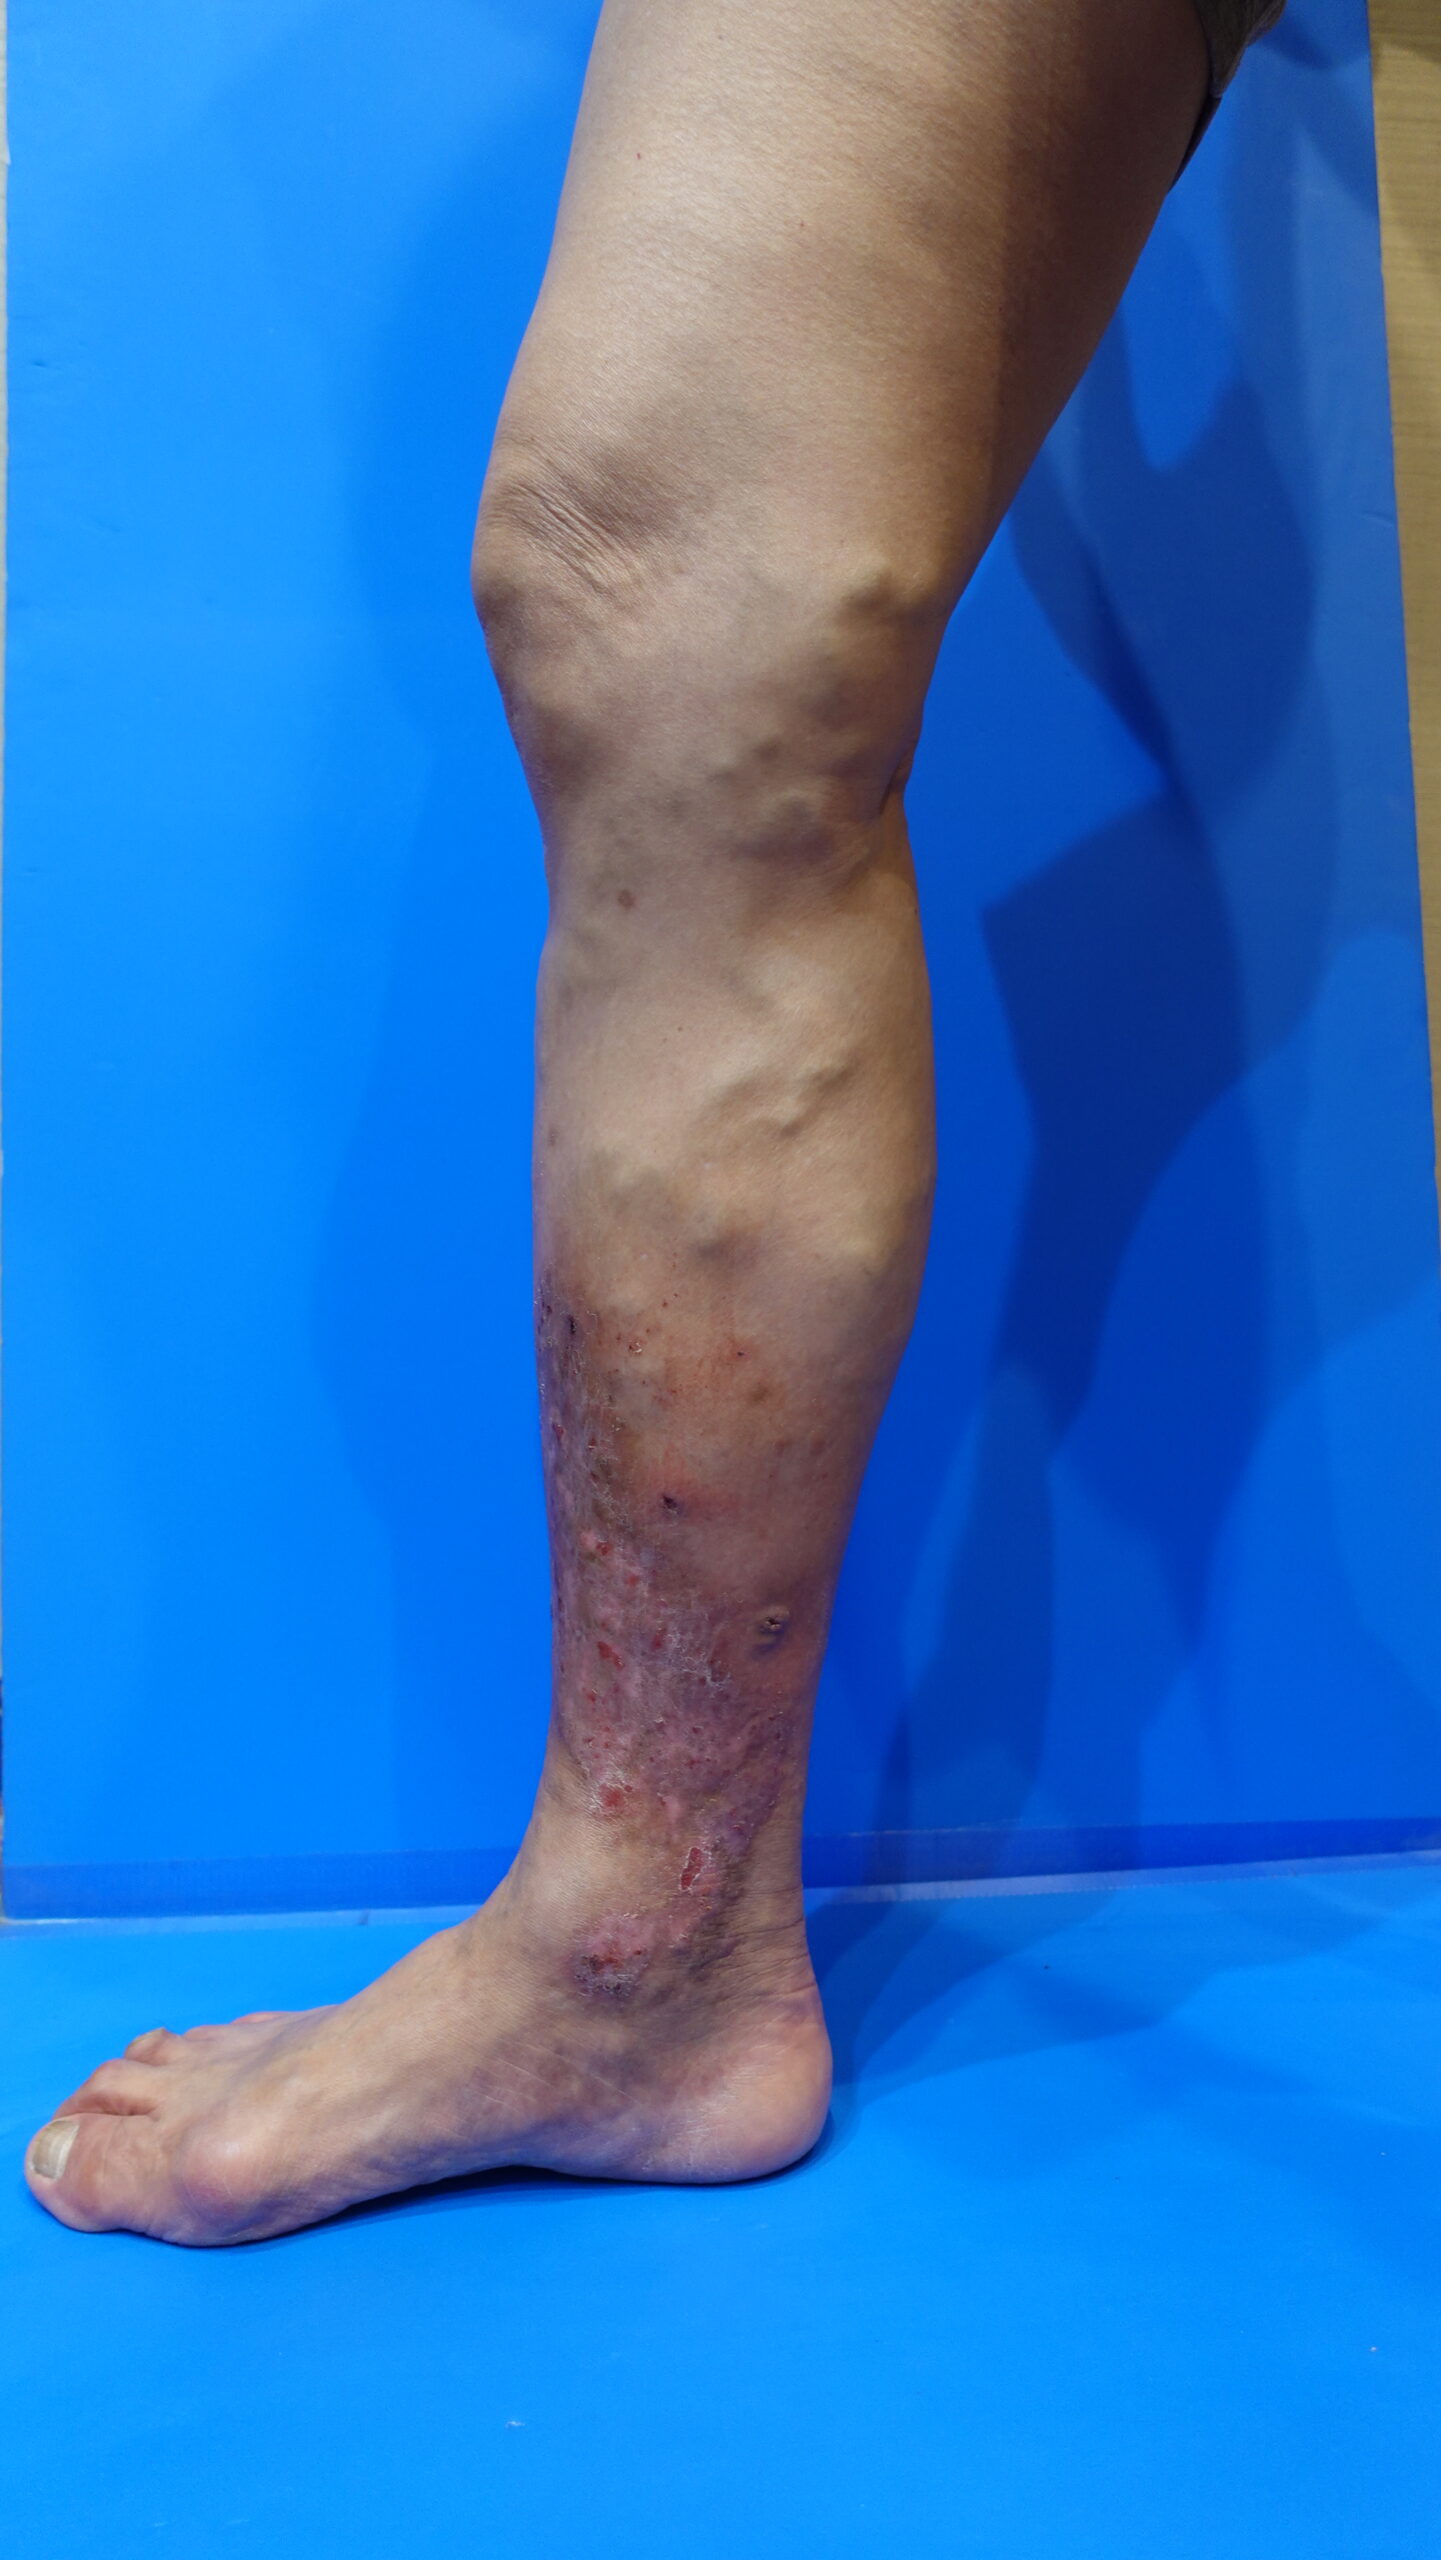

うっ滞性皮膚炎 湿疹

下肢静脈瘤 うっ滞性皮膚炎